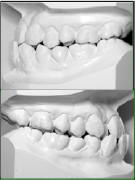

• 模型とその分析

• _